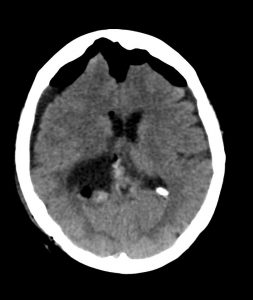

Η μετεγχειρητική αξονική τομογραφία εγκεφάλου δείχνει πλήρη αφαίρεση της βλάβης. Η ιστολογική εξέταση ανέδειξε μηνιγγίωμα WHO I.